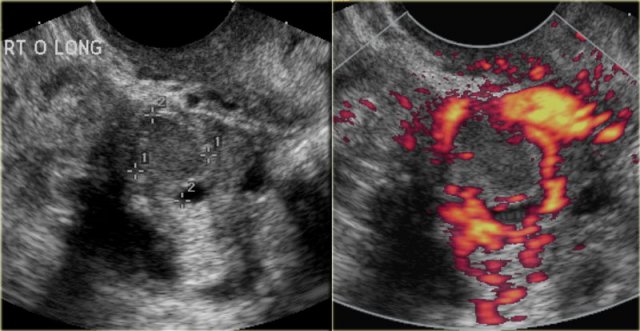

The transvaginal ultrasound images show a small complex ovarian cyst with wall vascularity on power Doppler analysis.

The characteristic circular Doppler appearance is called the 'ring of fire'.

Note, there is good through-transmission and no internal vascularity, consistent with a, partially involuted, corpus luteum cyst.

Corpus luteum cyst Corpus luteum cyst

Another case with the typical the 'ring of fire' on ultrasound.